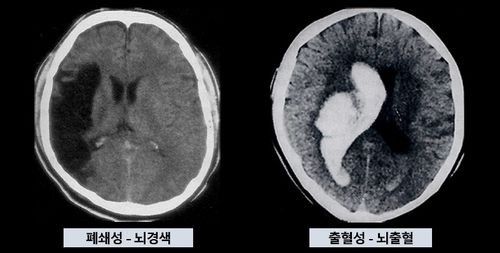

뇌경색과 뇌출혈 |